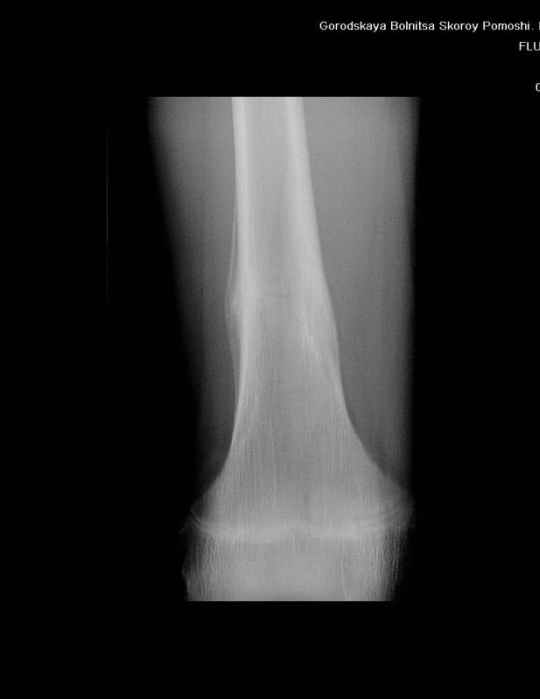

Анамнез практически никакой: в следствие травмы (растяжение связок коленного сустава) от 07.11.2004 выполнены Rg-граммы в травмпункте и обнаружено опухолевидное образование. Первичные Rg-граммы я не публикую, так как они заметно худшего качества, да и динамики за прошедшие три недели не отражают. Болевой синдром купирован в течение трёх дней. В настоящий момент мальчика ничего не беспокоит. Ходьба не нарушена, опухоль пальпируется с трудом по задней поверхности в н\3 правого бедра, пальпация безболезненна, объем движений в суставах правой нижней конечности полный и симметричный. Кожа над опухолью не изменена. В нашей клинике проведено дополнительное обследование: общие анализы крови и мочи, биохимия крови без особенностей. Выполнены Rg-граммы на цифровом Siemens обычные и продольные томограммы срезами 3-5 мм, а также компьютерная томография поперечными срезами по 5 мм. Прошу обратить внимание, что на приведённых томограммах видны две полости 10х15 мм и 15х60 мм. Также имеются два опухолевидных образований наслаивающихся друг на друга: уплощённое и вытянутое 10х100 мм и элипсовидной формы 15х30 мм. Это хорошо заметно на фото a_1.jpg c_1.jpg и d_1.jpg. Плотность внутри полостей 125% от плотности костномозгового канала, плотность наружного опухолевидного образования 55% от плотности кортикального слоя. Также отмечается линия перелома по центру наружного опухолевидного образования. Исходя из полученных данных мнения в плане диагноза несколько разделились от 1)сочетания кортикальной фиброзной дисплазии и латентно протекавшего маршевого перелома н\3 правого бедра до 2)остеосаркомы. В отношении первого варианта не сходится отсутствие клиники при переломе такой крупной кости как бедро, второй вариант вообще оставлю без комментария, ибо некомпетентен. Хотелось бы услышать мнения коллег, с удовольствием ознакомлюсь с любыми предположениями и замечаниями. С уважением, Александр Е. Клоков Отделение детской ортопедии и травматологии БСМП г. Мурманска.